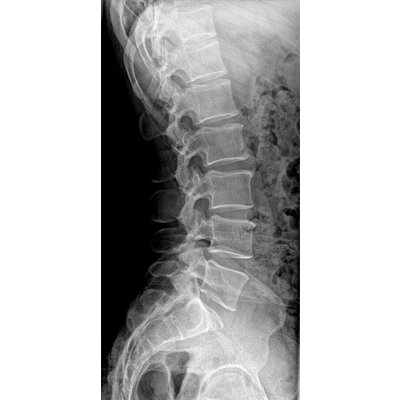

●大尺寸非晶硅平板探測器。

●非晶硅平板探測器,采用先進的制造工藝、性能更穩定。

●探測器可以大范圍轉動,大尺寸有效探測面積,可滿足人體多部位攝影需求。